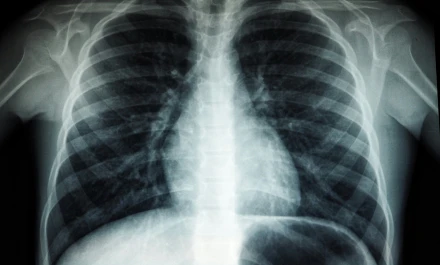

Καρκίνος πνεύμονα: Οι καθυστερήσεις διάγνωσης στην Ελλάδα μειώνουν τις πιθανότητες επιβίωσης

Ο καρκίνος του πνεύμονα παραμένει η πιο θανατηφόρα μορφή κακοήθειας παγκοσμίως, με εκατομμύρια νέες διαγνώσεις κάθε χρόνο και θνησιμότητα που ξεπερνά κάθε άλλη μορφή καρκίνου. Συγκριτικά, ο καρκίνος του μαστού εμφανίζει ανάλογη συχνότητα αλλά πολύ χαμηλότερα ποσοστά θανάτων, γεγονός που αναδεικνύει το τεράστιο κενό στην πρόληψη και έγκαιρη διάγνωση του καρκίνου του πνεύμονα. Σήμερα, μόλις ένας στους πέντε ασθενείς καταφέρνει να λάβει θεραπεία εγκαίρως σε εξειδικευμένα κέντρα, παρότι οι νέες θεραπείες, όπως η ανοσοθεραπεία, έχουν αυξήσει τις πιθανότητες επιβίωσης ακόμη και σε προχωρημένα στάδια.